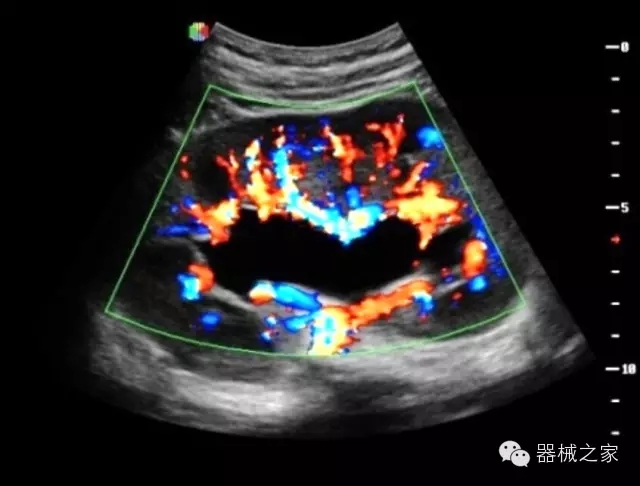

臨床圖片賞析

·獨有的HoloTM PW 實時3取樣門PW成像技術(shù),精確進行血管診斷;

·一鍵優(yōu)化B、Color、PW,Auto Doppler自動識別血管位置、偏轉(zhuǎn)角度等,提高工作效率;

·30°超廣角精細偏轉(zhuǎn)成像技術(shù),更優(yōu)異的頻譜圖像;

·智能微血流成像技術(shù):智能微血流捕捉技術(shù)可以提取出隱藏在背景噪聲中的弱血流信號,大大提高低速血流的敏感性;